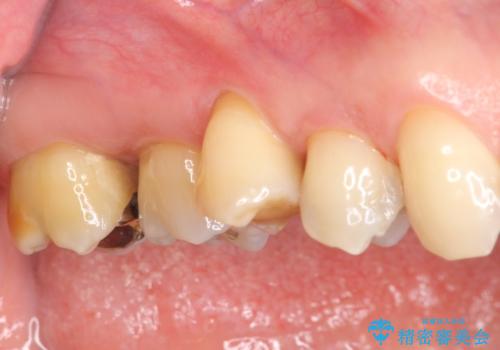

[歯周病治療] 再生療法で歯を残す②

担当医 大元洋佑

![[歯周病治療]  再生療法で歯を残す②の症例 治療前](https://seimitsushinbi.jp/wp/wp-content/uploads/2019/01/0ffdc5b1b2d07c4ae569ea27e1126f54-500x350.jpg)